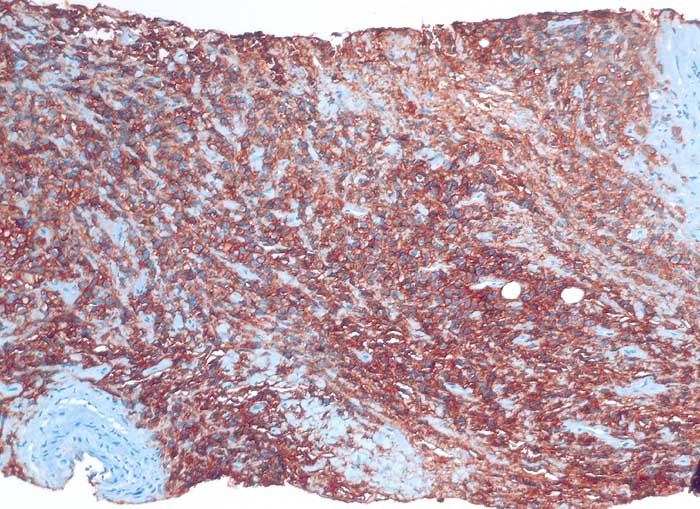

PathoPic ID 6394 - diffuses grosszelliges B-Zelllymphom

diffuses grosszelliges B-Zelllymphom

Nierenbecken

Nierenhilusweichteile: die Tumorzellen reagieren membranär positiv mit dem B-Zell Marker CD20.

Nieren-Tumor rechts. DD: Urothel-Ca.

Histologie

Immunhistochemie

CD20 (L26)

100